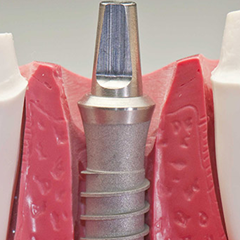

Implantologia

L’Implantologia Dentale è quella branca dell’Odontoiatria che si occupa di sostituire i denti mancanti con altrettante radici sintetiche ancorate nell’osso.